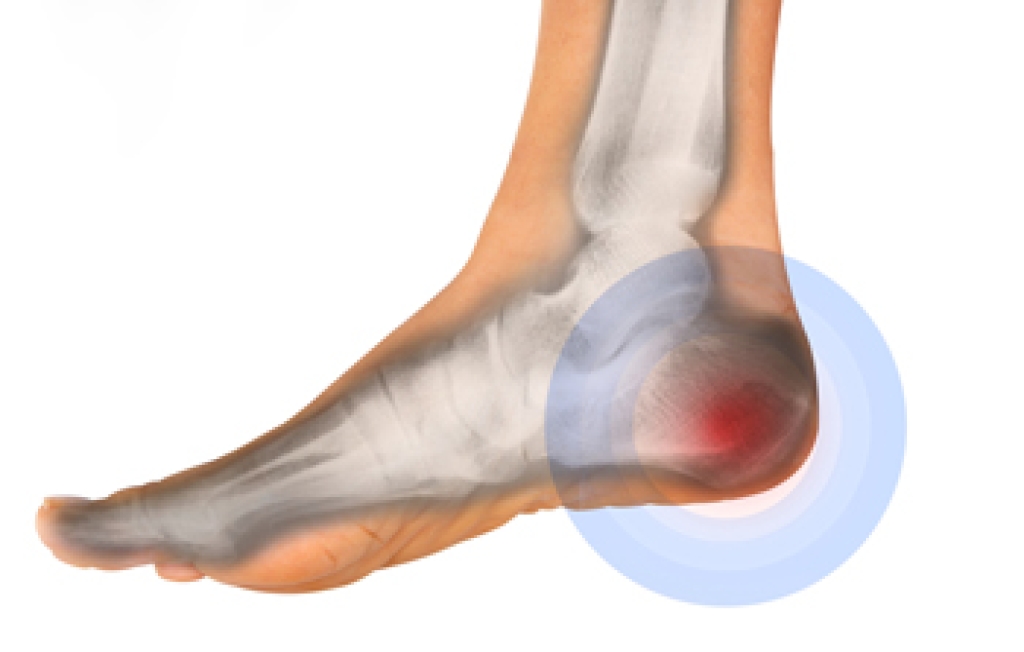

Swollen feet can also be caused by bone and tendon conditions, including fractures, arthritis, and tendinitis. Additionally, there may be skin and toenail conditions and an infection may cause the feet to swell. Patients who take medicine to treat high blood pressure may be prone to getting swollen feet.